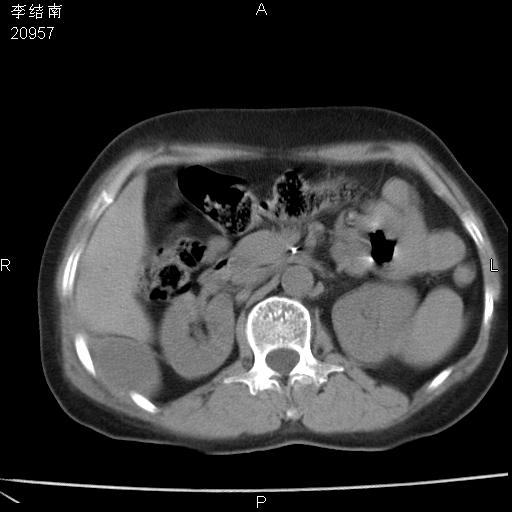

患者女,45岁,以右侧腰部包块来就诊,局部有压痛,皮肤颜色正常。因为是熟人扫的范围较大,患者有胆结石,胆源性胰腺炎病史。请大家看看,有手术病理。

可能大家觉得片子的质量不好,当时是做下腹部扫描,所以没有常规喝水,右腹壁的病灶当时是,密度不均有钙化影,局部骨质没见破坏,肝脏应该是受压的表现,所以当时考虑为腹壁的良性占位,各位老师考虑的神经源性肿瘤,我当时还真没想到,胰腺是胰腺炎治疗后改变.膈脚旁的混杂密度包快不好考虑什么,到上级医院做增强(腹部)+肺部平扫后,发现腹壁的病灶呈不均匀性强化局部可见囊性灶,当时考虑为腹壁结核,最具戏剧性的是膈脚旁的混杂密度灶确是胃的一部分,而腹壁的病灶确是脂肪瘤(简直不可思议)但是我亲眼所见在我们县医院开的.

很不好意思 ,患者后来手术切口裂开,临床医生作了病理证实是腹壁结核。

[病理诊断] CT13183腹壁结核!